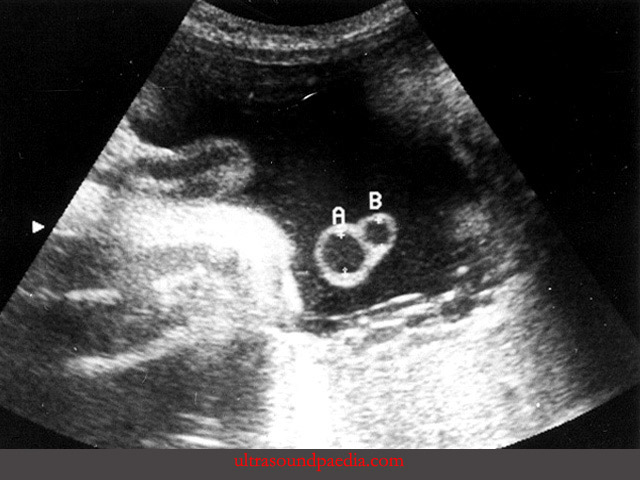

Cần hiểu đúng về cấu trúc dây rốn bình thường. Dây rốn thường có ba mạch máu. Gồm hai động mạch và một tĩnh mạch. Khi chỉ còn một động mạch, tình trạng này gọi là dây rốn một động mạch.

Dây rốn một động mạch thường được phát hiện khi siêu âm hình thái giữa thai kỳ. Ở giai đoạn này, mạch máu đủ lớn để quan sát rõ số lượng. Bác sĩ sẽ nhìn mặt cắt ngang dây rốn để đếm số mạch. Đồng thời kiểm tra mạch máu chạy hai bên bàng quang thai.

Nếu chỉ thấy mạch ở một bên bàng quang, đây là dấu hiệu đặc trưng của tình trạng chỉ còn một động mạch rốn. Cách kiểm tra này giúp tăng độ chính xác. Trong một số trường hợp, dây rốn xoắn nhiều hoặc hai động mạch dính đoạn ngắn gần bánh nhau có thể gây nhầm lẫn. Vì vậy, siêu âm kiểm tra lại là bước cần thiết trước khi kết luận.